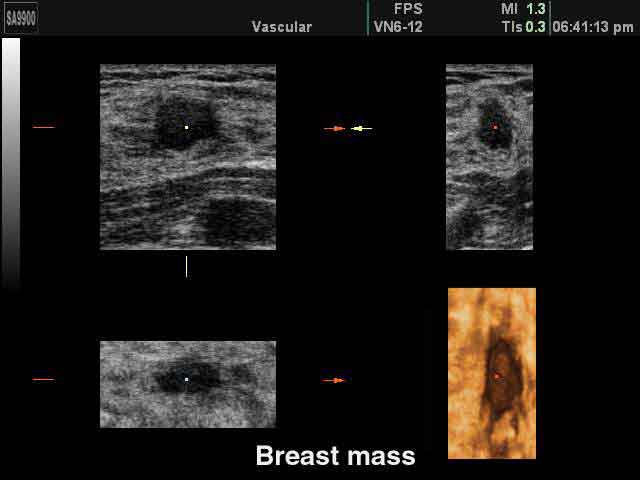

Tumore al seno: l’esame con ultrasuoni grande strumento preventivo

Oltre alle mammografie, le donne con un seno molto denso dovrebbero sottoporsi anche a un esame con gli ultrasuoni. Lo afferma al ‘Daily Telegraph’ un esperto britannico, secondo cui questo esame aumenterebbe la percentuale di scoperta di tumori del 42 per cento. “Le donne con una densita’ del seno superiore al 75 per cento hanno un rischio 4 volte maggiore di avere il cancro rispetto a quelle che la hanno inferiore al 25 per cento – ha spiegato Kefah Mokbel della London Breast Clinic – tuttavia queste donne vengono mandate a casa con l’affermazione che va tutto bene quando la mammografia e’ negativa.

Visto che e’ dimostrato che aggiungere gli ultrasuoni per le donne a rischio farebbe scoprire il 42 per cento dei tumori in piu’ migliaia di donne si potrebbero salvare introducendo questo esame”.

Un’alternativa agli ultrasuoni e’ sottoporre le donne a mammografia digitale, piuttosto che a quella tradizionale, afferma l’esperto, che e’ molto piu’ precisa nell’individuare anormalita’.